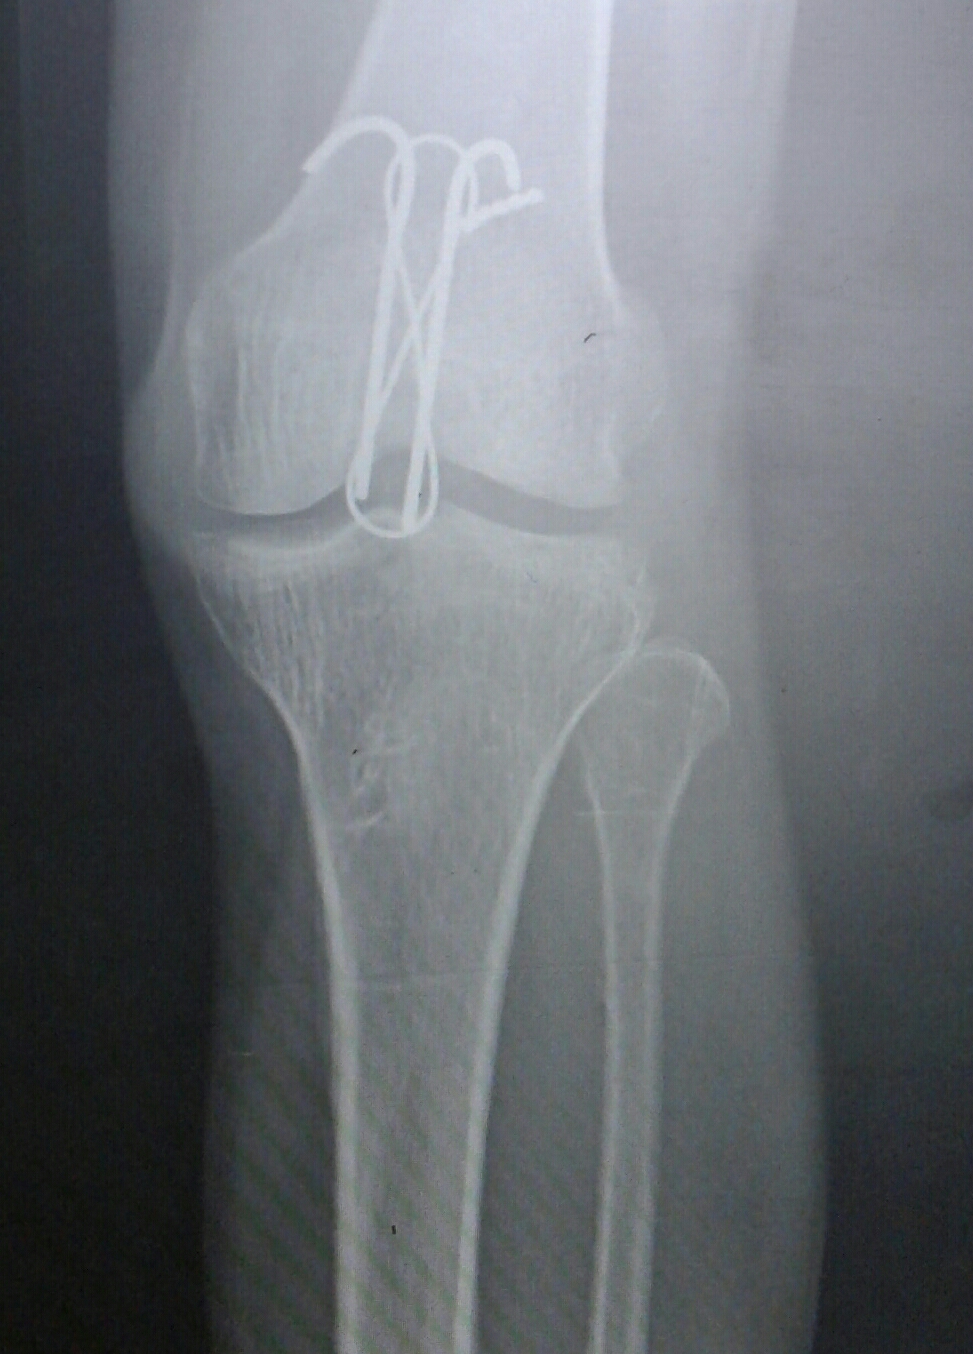

Patella fracture fixation in left knee, final intraoperative What Is Kneecap Fixation In most cases, a broken kneecap is caused by a direct blow to the front of the knee from a car accident, sports or a fall onto concrete. Falling directly on the knee, especially on a hard surface such as concrete. When knees get fractured, it’s often the kneecap (patella) that suffers the damage. There’s a good reason for that:. What Is Kneecap Fixation.